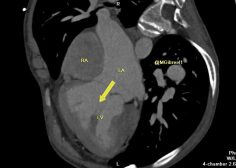

Criss-cross heart

Mohamed Gibreel , FEBR (Fellowship of Egyptian Board of Radiology ) Cardiac imaging consultant at Aswan heart center -Magdi Yacoub Foundation , Egypt